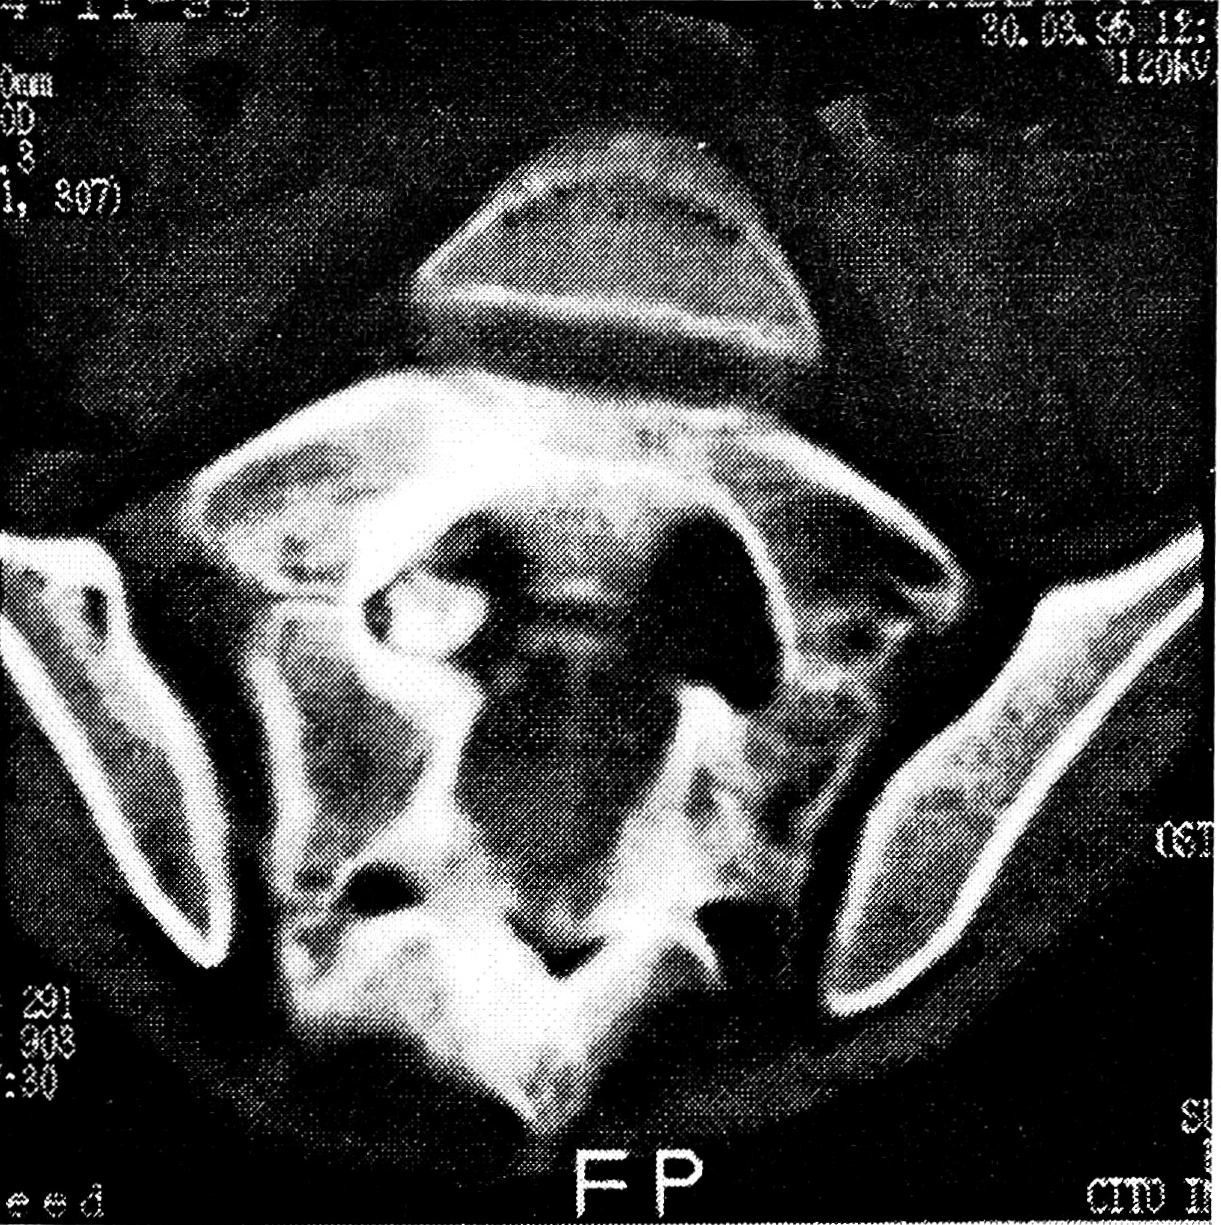

Рис. 5. Больная 12 лет с остеоид-остеомой S1 позвонка.

Компьютерная томограмма: интраканально расположенное «гнездо» остеоид-остеомы.